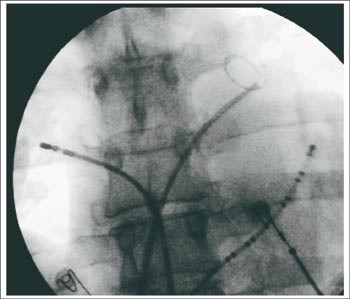

Anfallsvis atrieflimmer var dokumentert med EKG og/eller 24-timers-EKG hos alle (fig 1). Det ble gitt forbehandling med warfarin i fire uker, og vi tilstrebet INR-verdier på mellom 2 og 3. Warfarin ble seponert 2 – 3 dager før prosedyren. I lokalanestesi ble det utført hjertekateterisering med angiografi fra høyre atrium for visualisering av atriestørrelser og relasjoner. Transseptal punksjon ble utført, og en 8F føringshylse ble ført til venstre atrium. Gjennom denne ble et spesialkateter, betegnet «lasso» (slyngekateter), ført til en av lungevenene. Et radiofrekvensablasjonskateter ble ført gjennom samme punksjonshull til en av de andre lungevenene. Et 24-polet kateter ble plassert i sinus coronarius og langs trikuspidalringen for elektrisk stimulering og registrering av elektrisk aktivitet i begge atrier (fig 2).

Det ble gitt intravenøst heparin under prosedyren. Etter plassering av elektrodekatetre ble ev. pågående atrieflimmer elektrokonvertert i generell anestesi. Pasienten ble så monitorert i sinusrytme med og uten isoprenalininfusjon 3 – 5 µg/min for å fremkalle fyringer fra ektopiske foci i lungevener eller atrier (fig 3). Under sinusrytme og stimulering bedømte vi også om det forelå lokale elektrogrammer i lungevenene som tegn på muskelforbindelse til atriet.

I utgangspunktet ble alle fire lungevener forsøkt isolert. Hvis det ble observert fyring fra en bestemt vene, ble denne isolert først og etterkontrollert sist i prosedyren. Ablasjon ble utført der kartleggingen med slyngekateter langs ostiene viste ledning mellom atriet og den aktuelle lungevene, til isolasjon ble bekreftet med bortfall av elektrogram i lungevene (fig 4). Hvis ytterligere foci ble påvist utenom lungevenene, ble disse også forsøkt ablasjonsbehandlet i samme seanse. Hos 43 pasienter ble det på forhånd eller i samme seanse også utført ablasjonsprosedyre for type I-atrieflutter i høyre atrium (3).